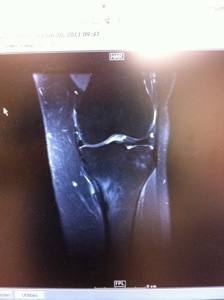

In January of 2011, I made a major decision to join weight watchers. Best decision I ever made, but also bitter sweet. I had been in Colorado over the Christmas holiday, I went for a run on Christmas morning and thought I pulled something, I found out several weeks later that I had fractured my leg…